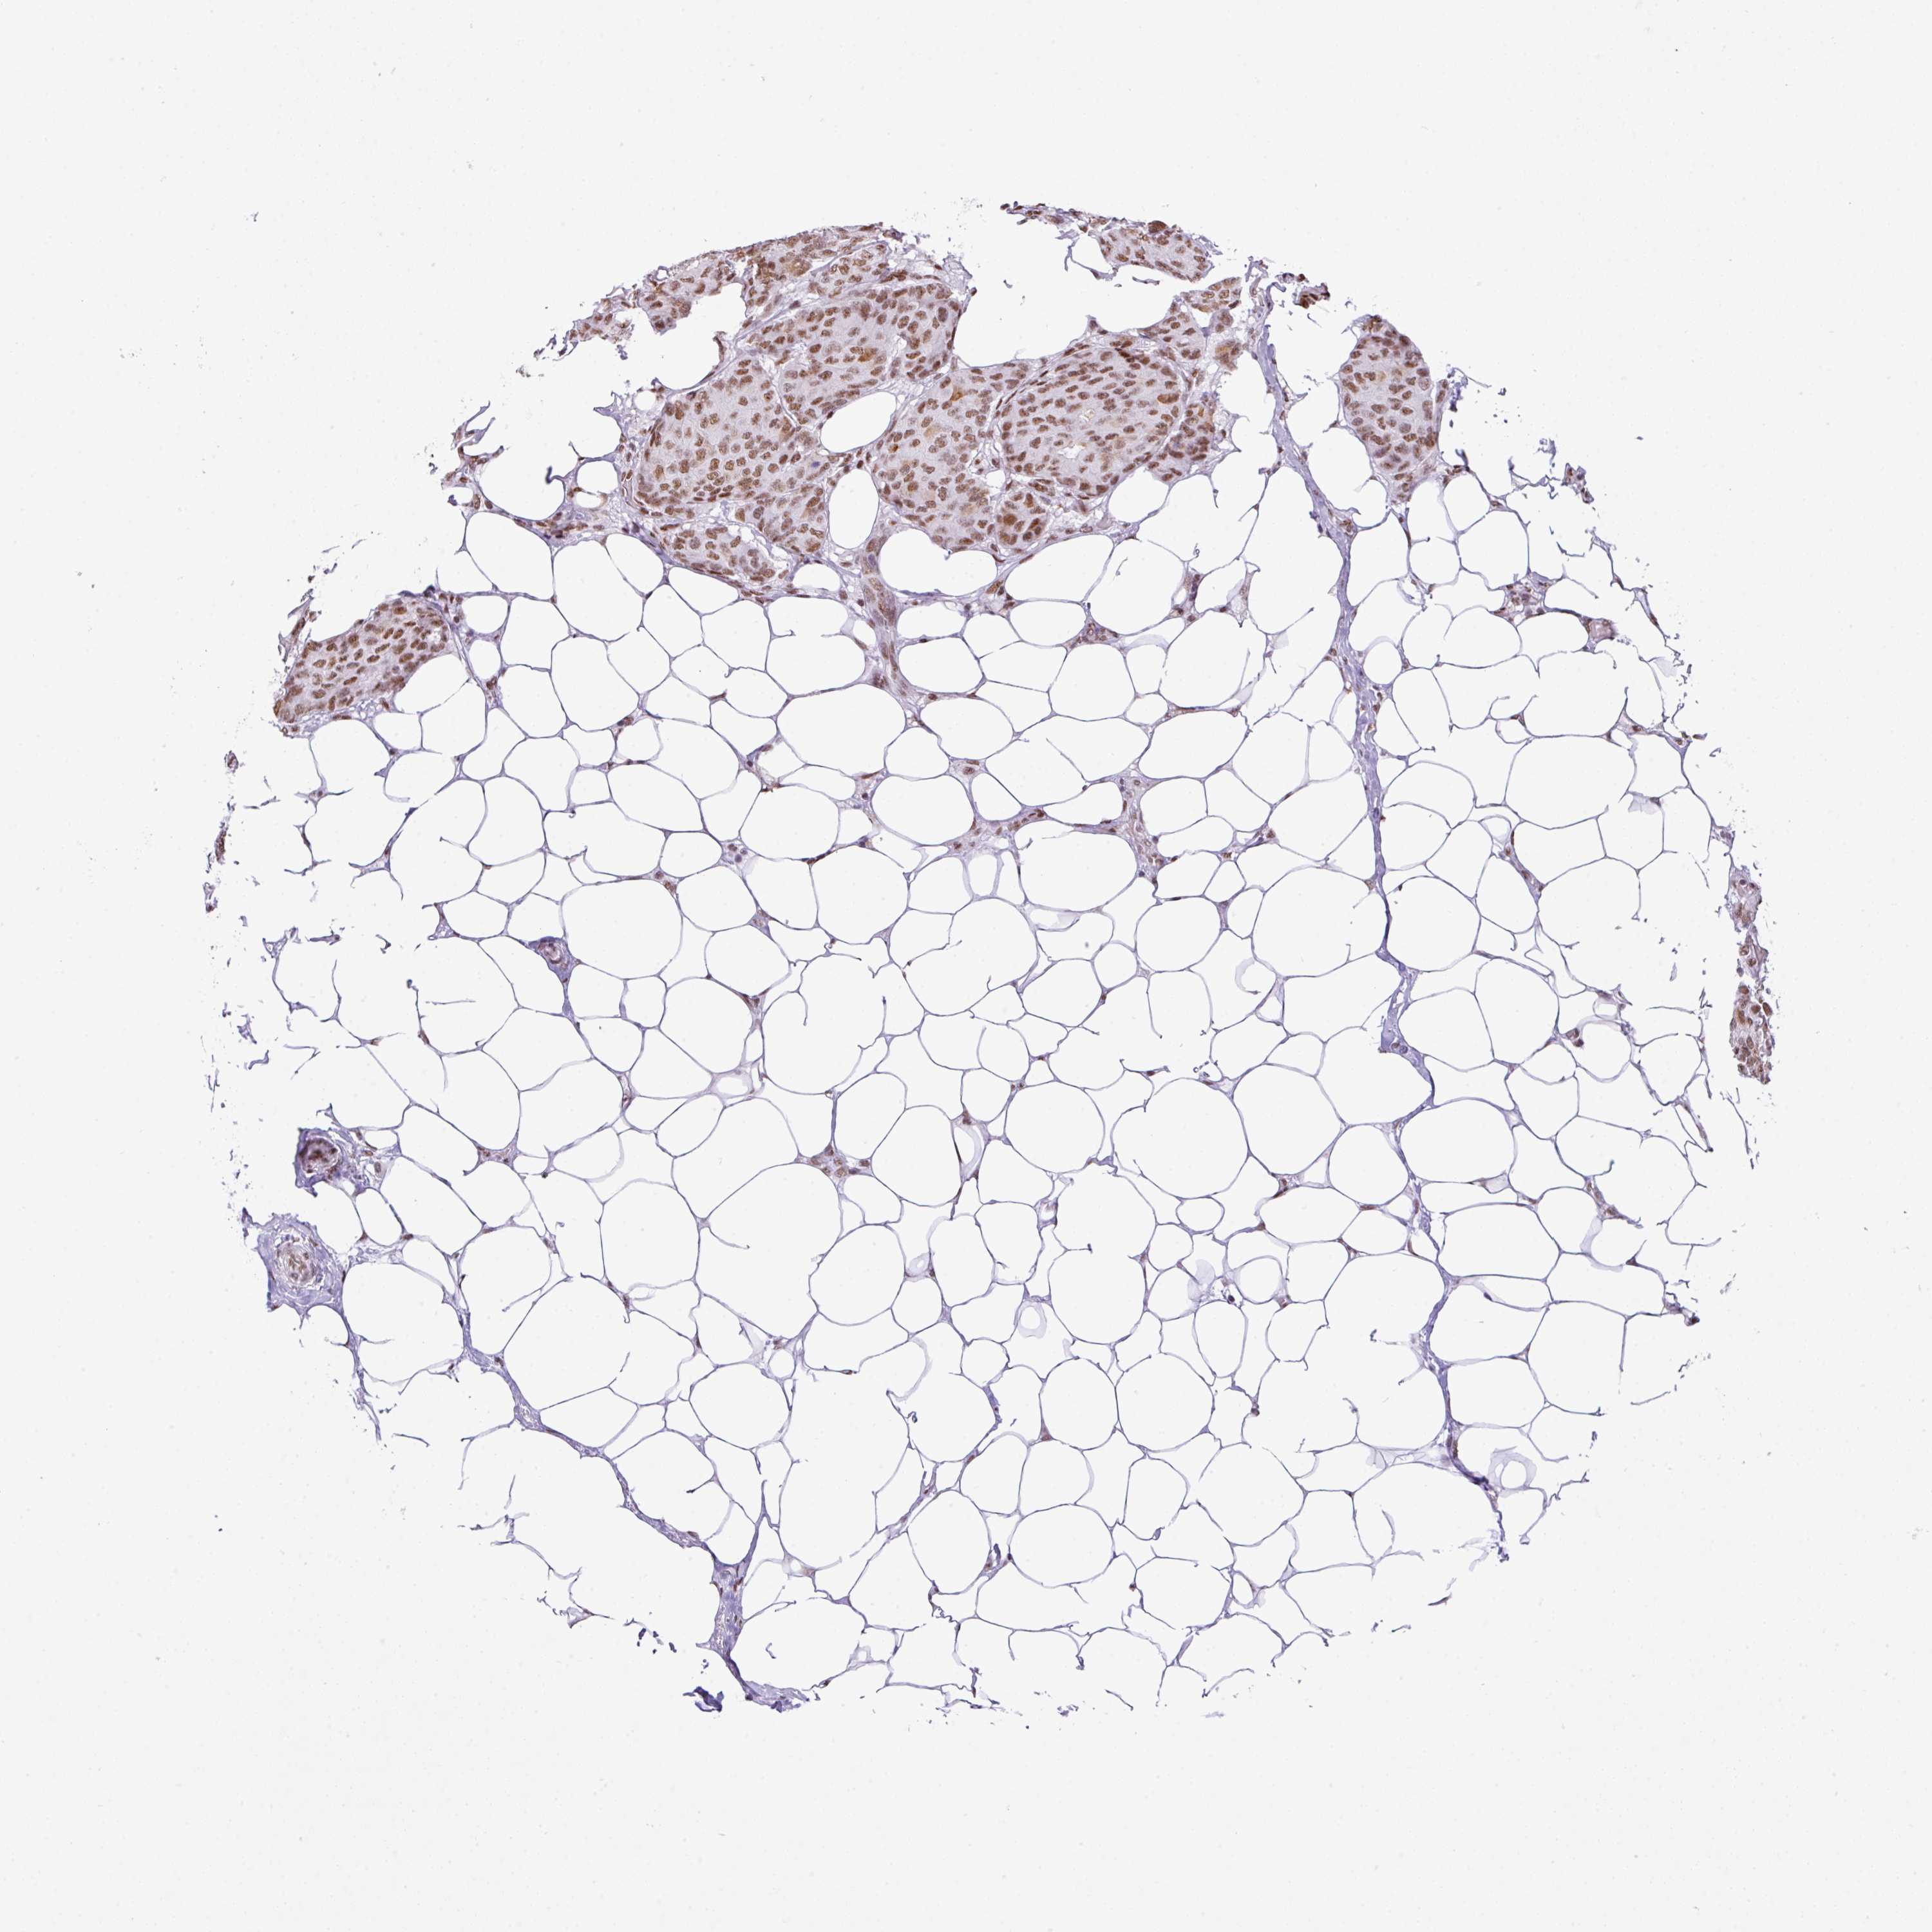

BRCA TCGA BRCA VALIDATION PROTEIN EXPRESSION

ANTIBODIES

AND

VALIDATION